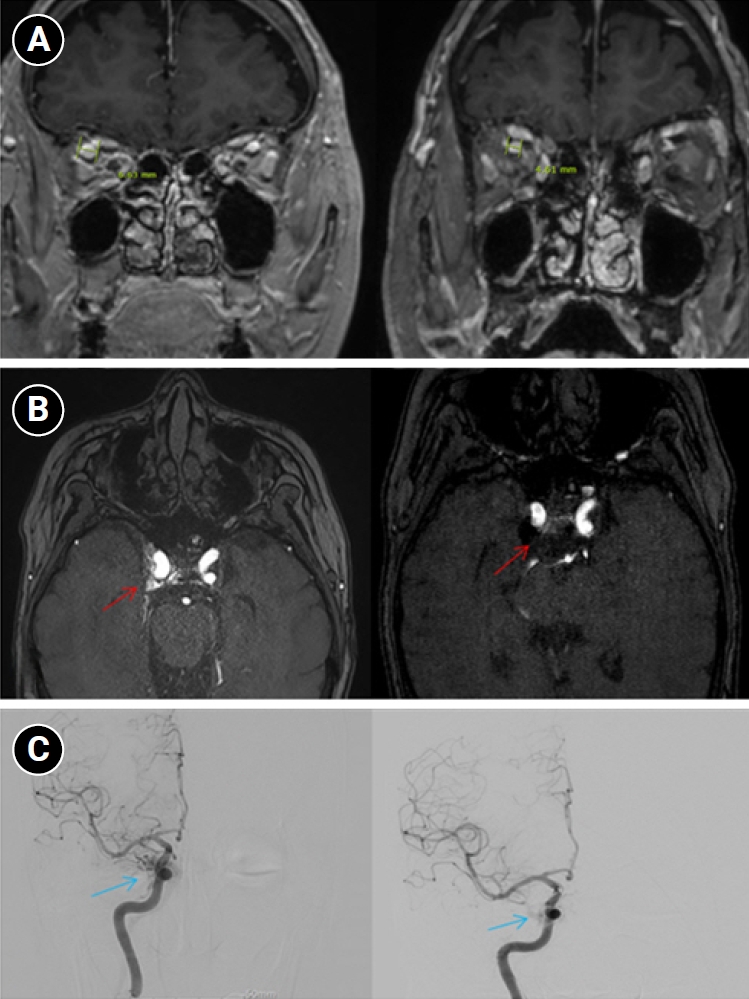

Baseline hematology and chemistry—including complete blood count, electrolytes, renal/hepatic indices—and coagulation tests (prothrombin time/international normalized ratio, activated partial thromboplastin time) were within reference limits. Erythrocyte sedimentation rate and C-reactive protein were normal. A focused screen for secondary trigeminal neuropathy (thyroid-stimulating hormone, vitamin B12, HbA1c) was negative. There were no clinical signs of infection. Brain magnetic resonance imaging (MRI) demonstrated high flow related signal in the right cavernous sinus and asymmetric dilation of the superior ophthalmic veins (right>left), raising suspicion for a CCF (Figure 1). Definitive diagnosis was established on digital subtraction angiography (DSA), which identified a right CCF. DSA demonstrated an indirect CCF supplied by the right meningohypophyseal trunk of the ICA and by right ECA branches, including the internal maxillary artery and the cavernous branch of the middle meningeal artery, consistent with Barrow type D (Figure 2).6 Barrow type D denotes an indirect, low-flow fistula with dual ICA/ECA dural supply; unlike direct type, indirect types present more insidiously, and symptom patterns are largely determined by venous drainage, with posterior drainage often manifesting as CN VI palsy and headache (Table 1).1,3,6,7 The fistula was treated with transvenous Onyx embolization. On post-procedure day 1, non-contrast time-of-flight magnetic resonance angiography (TOF-MRA) demonstrated a marked reduction of flow related hyperintensity within the right cavernous sinus, and the right superior ophthalmic vein caliber decreased from 6.63 to 4.61 mm (Figure 3A, B). Follow-up DSA (at 3 weeks) likewise showed substantial attenuation of fistulous opacification (Figure 3C), supporting a significant interval decrease in arteriovenous shunting. At 1–2 weeks, the patient reported an ~80%–90% reduction in dental/lower-facial pain and bifrontal headache from NRS 7–8 to 1–2. By 1 month, red-glass testing demonstrated resolution of primary-position diplopia. Formal prism measurements were unavailable; bedside ocular-motor grading was recorded using a standard duction underaction scale (–4 to 0). Right abduction improved from –1 to 0, and primary-position diplopia was absent at distance and near, consistent with recovery from abducens palsy.

Imaging changes before and after embolization. (A) Brain magnetic resonance imaging (coronal section through the orbits) shows a decrease in the diameter of the right superior ophthalmic vein from 6.63 mm pre-embolization to 4.61 mm post-embolization, indicating reduced venous congestion. (B) Axial time-of-flight magnetic resonance angiography demonstrates that flow-related hyperintensity within the right cavernous sinus is markedly reduced after embolization (red arrows), consistent with decreased shunt flow. (C) Digital subtraction angiography images before embolization show abnormal early pericavernous venous filling along the right cavernous sinus region (blue arrows), compatible with carotid-cavernous shunting. On follow-up, this abnormal filling is no longer visualized, consistent with interval reduction in shunt flow.

According to prior literature, posteriorly directed, high-pressure venous drainage in indirect CCFs can precipitate venous congestion around Meckel’s cave, providing a substrate for V2/V3 territory pain; this builds on earlier evidence implicating vascular compromise at the trigeminal (Gasserian) ganglion level.4,5 In our case, the post-procedure reduction in TOF-MRA flow related signal, along with decreased superior ophthalmic vein engorgement, indicates reduced cavernous venous pressure, plausibly relieving congestion around Meckel’s cave and thereby improving V2/V3 pain. The bifrontal, pressure-like headache with nausea/vomiting can be explained by posteriorly directed venous outflow from the fistula, which produces venous hypertension in the cavernous sinus and posterior dural venous pathways.1,3,7 Resultant venous engorgement distends pain-sensitive dura and activates trigeminal meningeal afferents, yielding a secondary dural headache rather than a primary migraine phenotype; the bifrontal topography is compatible with referral from the anterior cranial fossa/cavernous region dura via the ophthalmic and maxillary divisions.1,7 In line with this mechanism, headache occurs more often in indirect CCF than in direct CCF, reflecting posterior venous drainage and dural venous hypertension. Correspondingly, headache improvement tracked with the post-embolization decrease in shunt on TOF-MRA, supporting a venous-driven mechanism linked to posterior drainage. Likewise, abducens palsy—given the nerve’s central course through the cavernous sinus and vulnerability near Dorello’s canal—would be expected to improve as cavernous venous hypertension resolves, consistent with the observed normalization of right abduction on bedside duction grading.

In indirect CCFs as in our patient, endovascular therapy was selected as first-line; if endovascular access is not achievable or durable occlusion cannot be obtained, surgical management may be required.2,3 Given the indirect (Barrow D) angio-architecture, a transvenous approach—typically via the inferior petrosal sinus or, if inaccessible, the superior ophthalmic vein—was preferred, as transarterial embolization of dural feeders in indirect CCFs is associated with a higher embolic stroke risk.6,7 Transvenous embolization is commonly favored for indirect CCFs given the relatively straightforward venous anatomy, and high angiographic occlusion rates have been reported. Overall, endovascular treatment across techniques and access routes yields clinical improvement in approximately 60%–95% of cases.10 Post-embolization TOF-MRA demonstrated a marked reduction of flow related signal in the right cavernous sinus with decreased superior ophthalmic vein engorgement, consistent with interval shunt reduction and accompanied by ~80%–90% relief of dental/facial pain and improvement in diplopia. As shunt flow decreased, the V2/V3 territory pain improved in parallel, supporting the fistula as the proximate source of the pain.